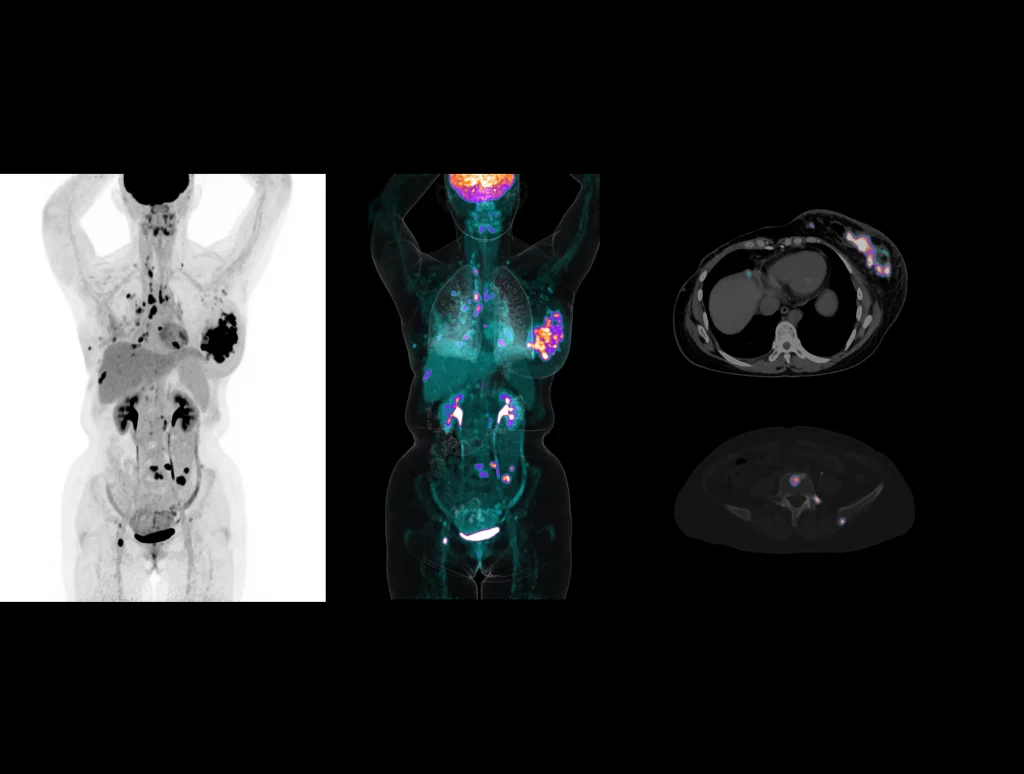

With the ultra-high system performance, uMI Panorama faces up to the challenges of tracers with different half lives and the complex scanning conditions, without compromise for image quality.

New-Tracer Imaging

Click on different tracers to see the images.